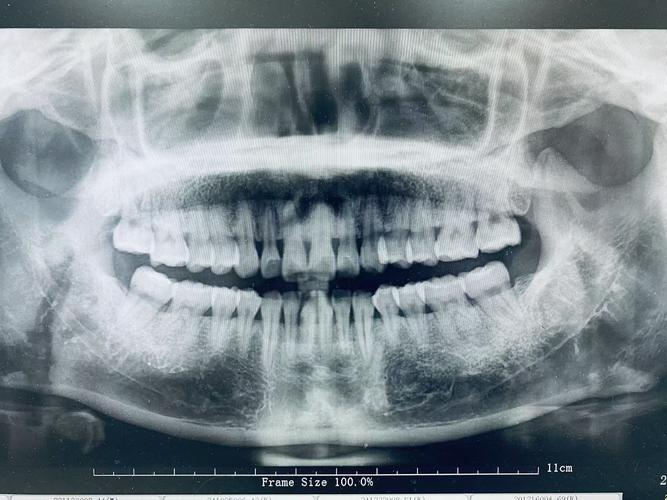

(图片来源网络,侵删)- 知情同意:向患者解释拍摄目的、过程及注意事项,缓解紧张情绪,取得配合。